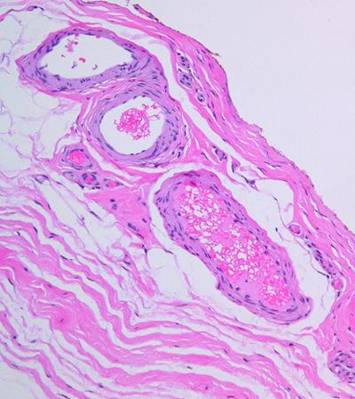

Figure 14   (right)

(a, top left)  Normal reticular dermis.  Large, parallel, mostly transverse collagen bundles are separated by interstitial spaces.  Typical fibroblasts in typical densities are dispersed throughout

(b, top right)  Normal reticular dermis from another subject.  There is variability in the size and orientation of dermal collagen from specimen to specimen, due to location, skin thickness, local biomechanics, orientation of the specimen cuts relative to local skin anisotropies (Langer’s lines, fibers seen parallel or on end), and intersubject variability.  Thus the two top specimens look different, but both are normal reticular dermis.  Collagen bundles are large, somewhat coiled, wavy, or springy.  They are largely individualized and distinct, separated by interstitial spaces.  These factors permit elastic compliance of the material, and normal motion of related body parts

(c, middle left)  Young scar.  This is normal repair at peak fibroplasia.  The scar is highly cellular, and in ensuing weeks it will become heavily collagenized.  Dense packing of fibers means no fluidity of the material.  Lack of folding or waviness means that there can be no distensibility.  This is the stuff that causes contractures, strictures, stenoses, stiffness, and other typical adverse effects of scar.

(d, middle right)  Young Integra.  In comparison, young Integra has a completely different histology, morphology, and biomechanics.  The matrix itself partitions the collagen, having a similar effect on the structure and mechanics of the material that the interstitial spaces have in normal dermis.  While it does not look precisely like normal dermis, it has many of the same structural properties, and it can be expected to behave like normal dermis.

(e, bottom left)  Matured scar.  This scar, at 2 years old, is still cellular compared to normal dermis, but not by much.  The scar collagen has undergone a gradual transformation.  It is now bundled and springy, looking mostly like normal dermis.

(f, bottom right)  Old Integra at 4 years.  The original matrix is largely gone in this area (but it is still abundant in some other out-of-view areas of this biopsy).  For septae that do remain, their morphology is still unaltered.  Just as with scar, normal physiological collagen remodeling is also slowly making this specimen look like normal dermis.  However, in sharp contrast to scar, Integra has, from the outset, a structure and properties that are already very close to dermis, thereby avoiding scar complications.